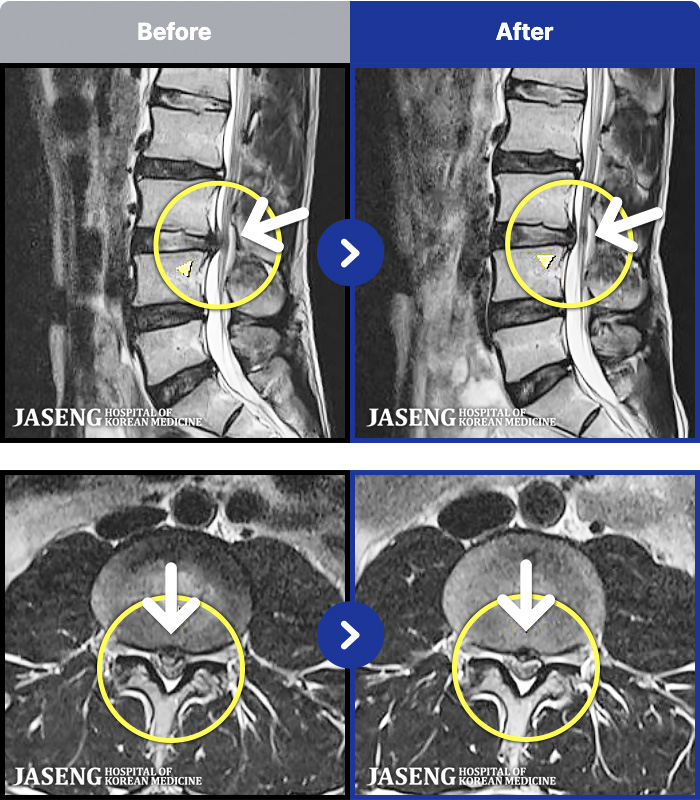

MRI ġ

1,301 MRI ũ ʸ Ȯϼ.